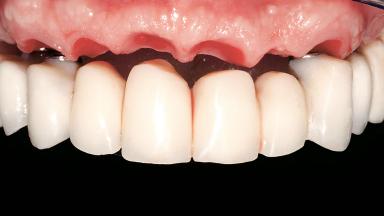

A 63-year-old male patient was referred for a consultation and treatment of partial edentulism in the maxilla. The patient presented with residual anterior teeth and declined a partial removable prosthesis. He reported that the maxillary posterior teeth had been extracted due to mobility and periodontal disease two months before the consultation. The patient’s chief complaint was that his residual maxillary teeth were mobile and that he was unable to chew. The patient’s desire was a stable and comfortable fixed maxillary rehabilitation. The patient was a light smoker (fewer than 10 cigarettes/ day), and his medical history was without significant findings. He was not on any regular medication at the time of consultation. The extraoral examination revealed a normal physiognomy with a correct distribution of the facial thirds. The patient presented a low lip line, and the transition line between teeth and soft tissues was not exposed during a forced smile.